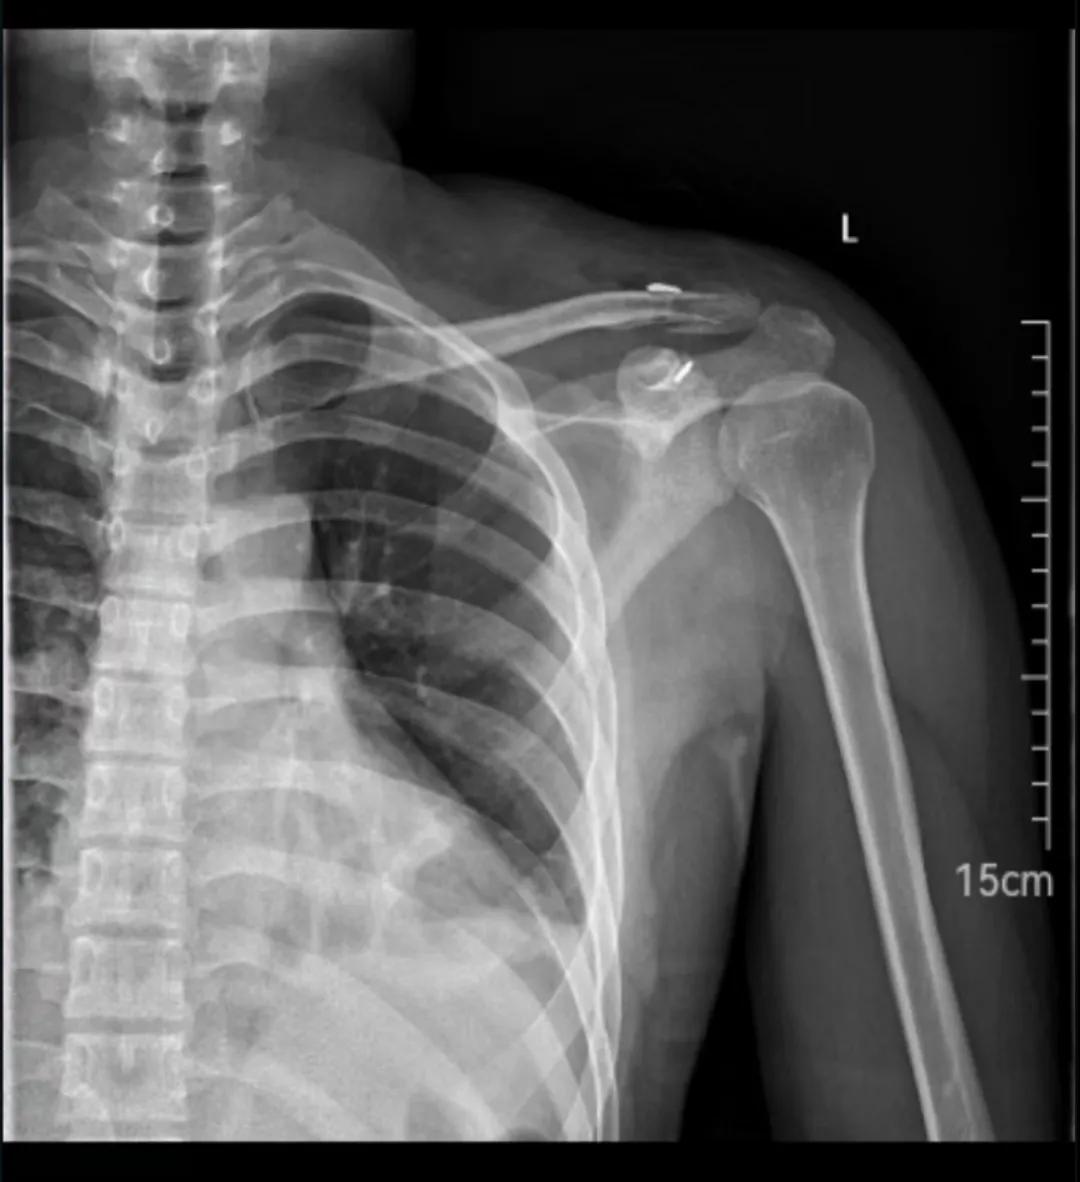

锁骨远端骨折

锁骨远端骨折切开复位袢钢板内固定

患者是个高三学生,还有40多天就要高考了,锁骨远端骨折,做了切开复位袢钢板内固定术,术后伤口出现了感染。现已术后第十天,伤口已开裂,深部有渗出。感染再发展下去可能就要耽误高考了。当前主要矛盾是控制感染,尽可能地让患者早日回归教室,参加高考。